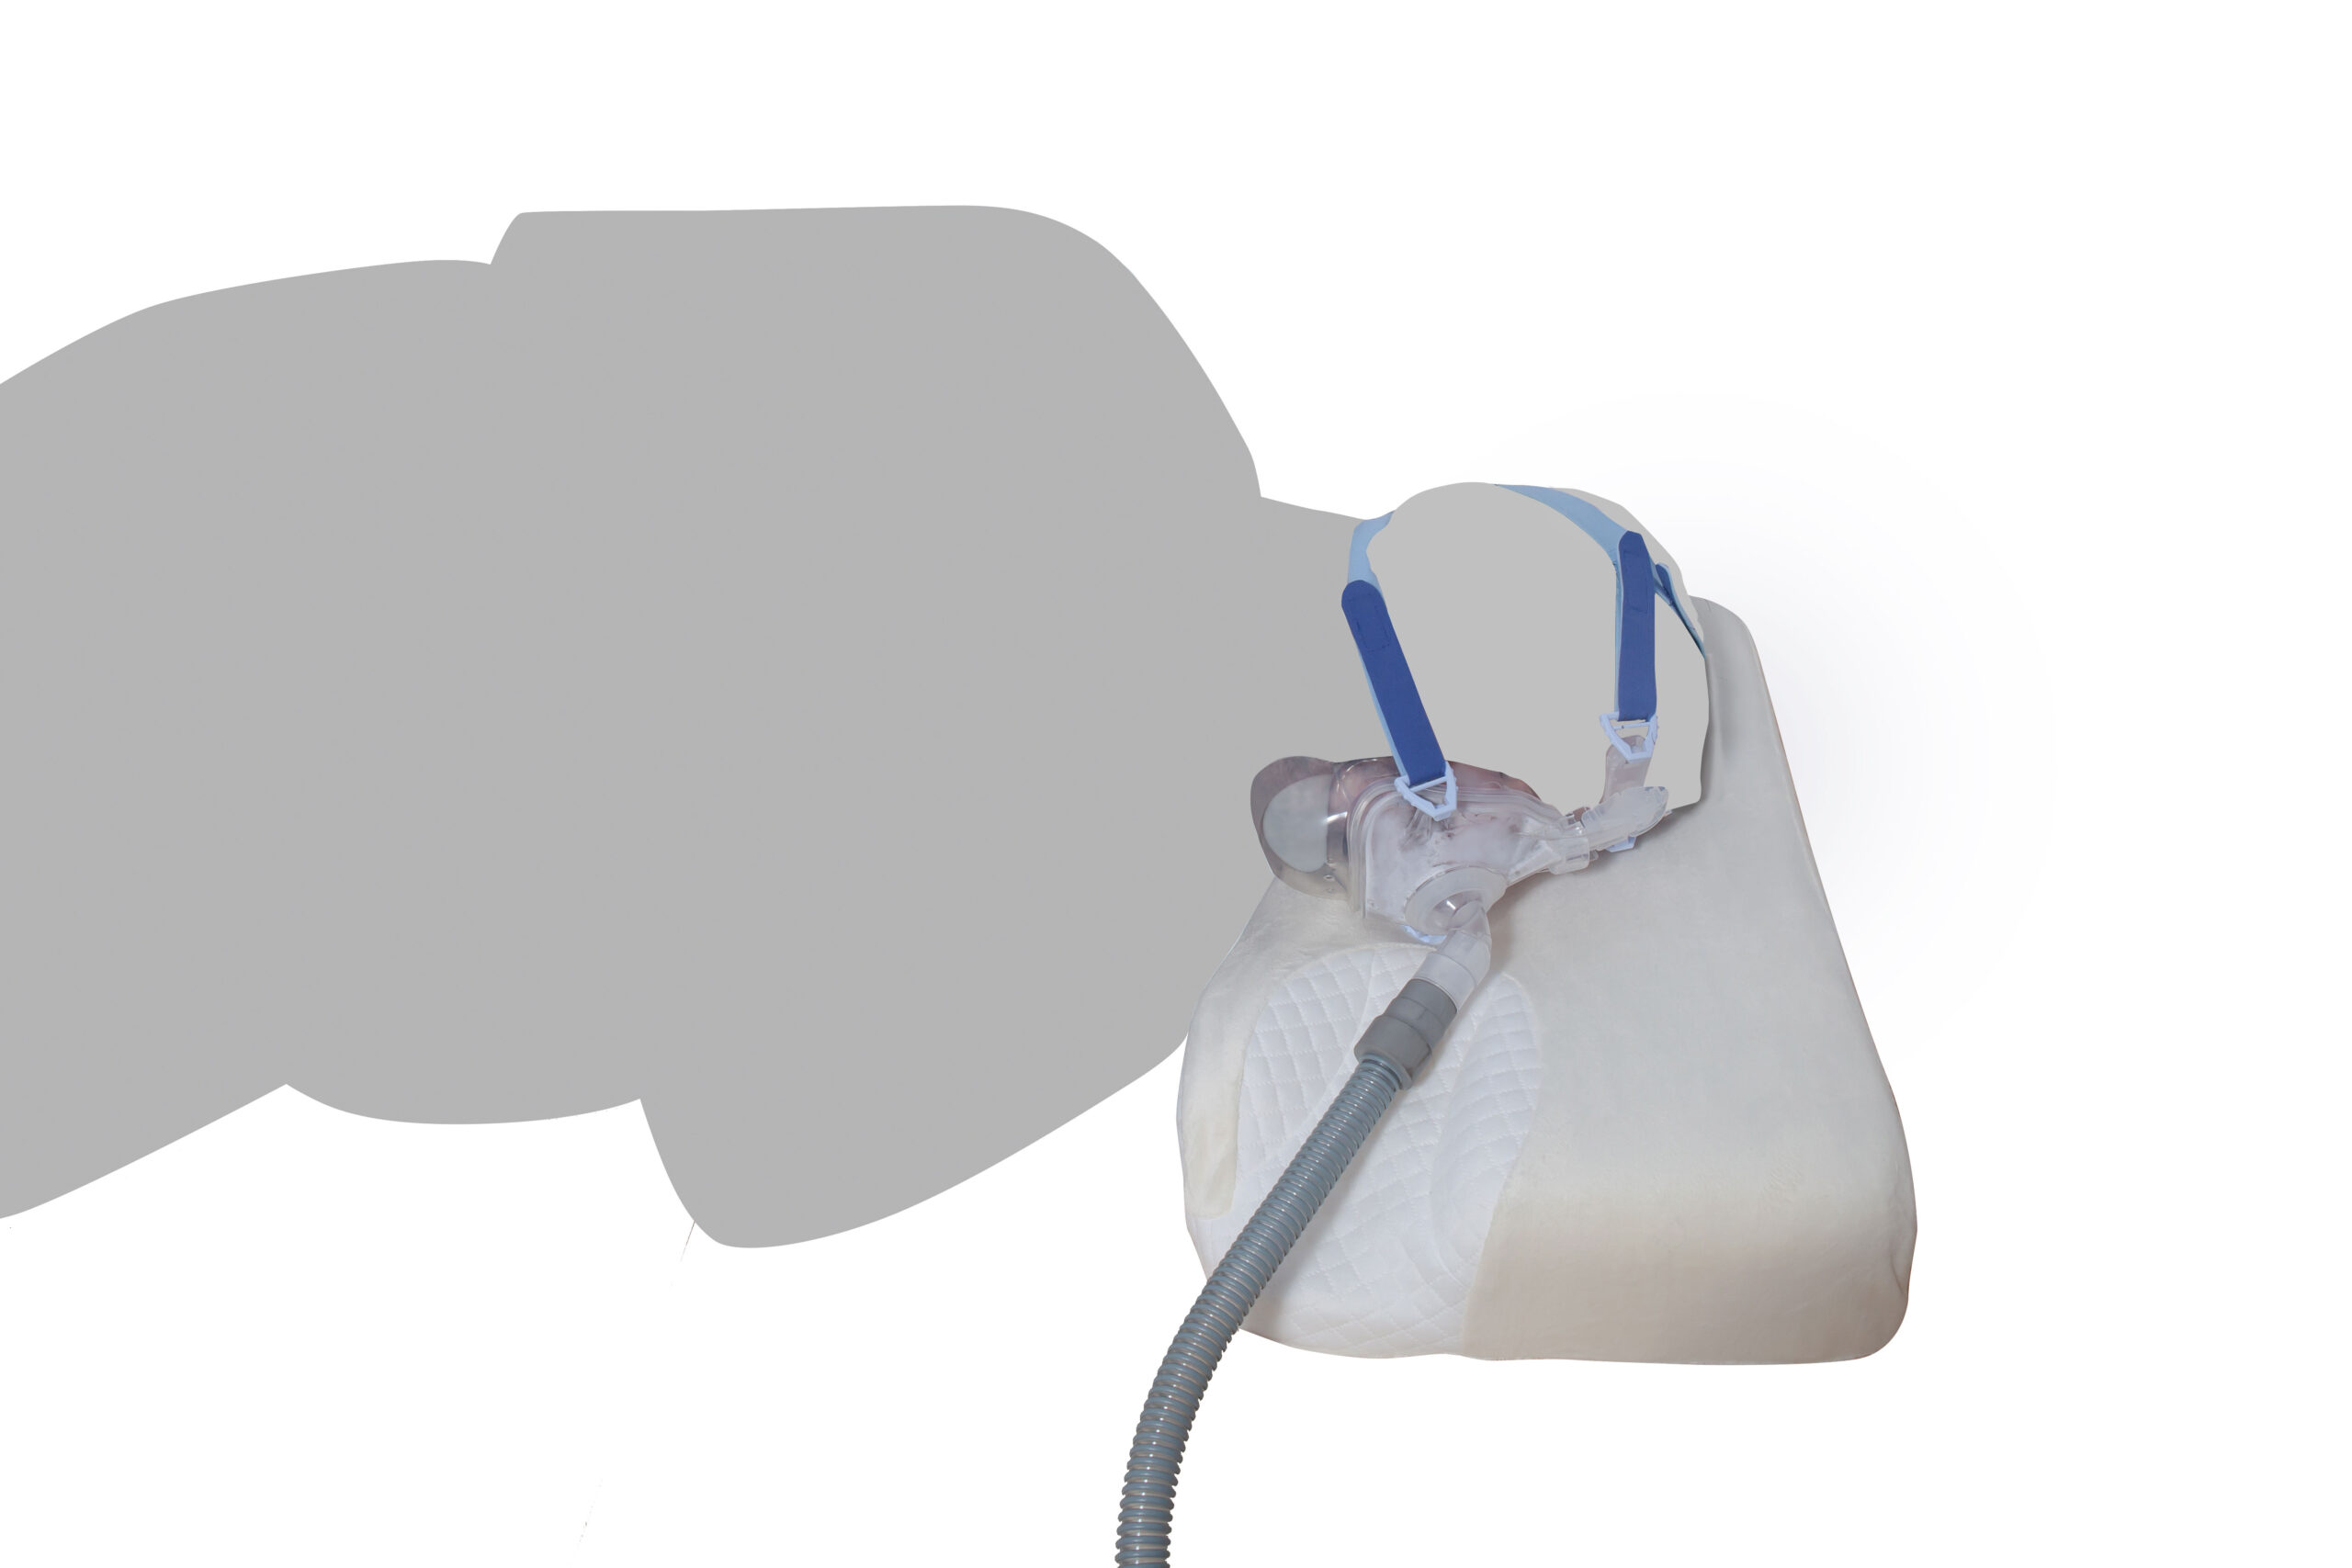

• Για Χρήση με Συσκευές Άπνοιας, Μειώνει την Πιθανότητα Διαρροών από την Μάσκα από το Λύγισμα του Σωλήνα

• Στηρίζει Αυχένα και Λαιμό

• Διαθέτει Ειδικό Σχήμα Στήριξης Κεφαλιού στο Κέντρο

• Διαστάσεις (ΜxΠxΥ): 50 x 32 x 10 cm